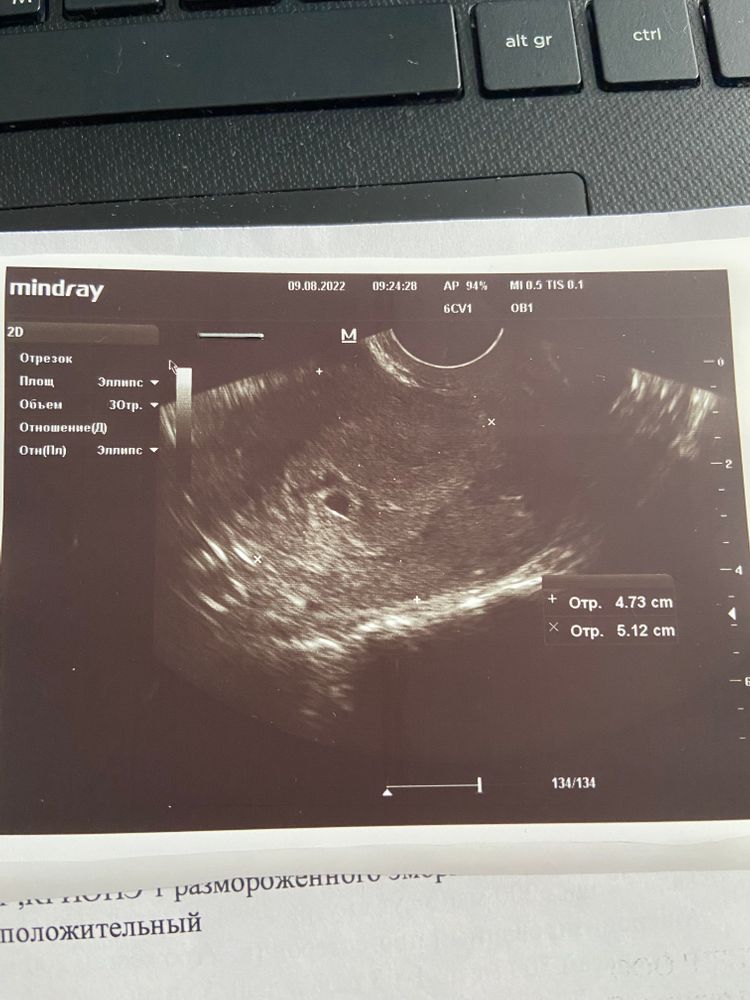

21дпп. Первое УЗИ.

09.08.2022